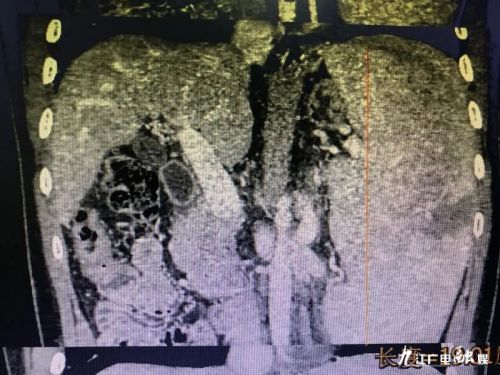

患者男性,22岁,因腹胀、双下肢浮肿2天就诊于生命活水医疗集团消化内一科。该患者6年前诊断为肝硬化失代偿并脾功能亢进,近年来曾到国内多家三甲医院就诊,均未查明脾亢原因。此次入院诊断为:1、脾大伴脾功能亢进 2、脾梗死 3、肝硬化失代偿期 4、慢性肝功能衰竭 5、门脉高压 6、慢性胆囊炎 7、门脉高压性胃病 8、腹水。腹部彩超见脾脏肋间厚约85mm,脾210mm,大小为正常人的近8倍。血小板:21×10^9/L,仅为正常值的1/10,有严重的内脏出血倾向。经护肝、利尿等对症治疗后,患者腹胀及浮肿症状得以好转,但血小板、白细胞减少的问题却无法解决,仍存在出血、免疫力低下等风险。经许剑峰会诊后,建议行腹腔镜巨脾切除术+腹腔镜肝组织活检术。既可以解决患者脾功能亢进所导致的血小板、白细胞减少问题,还可以术中取肝组织行病理检查,明确肝硬化病因。